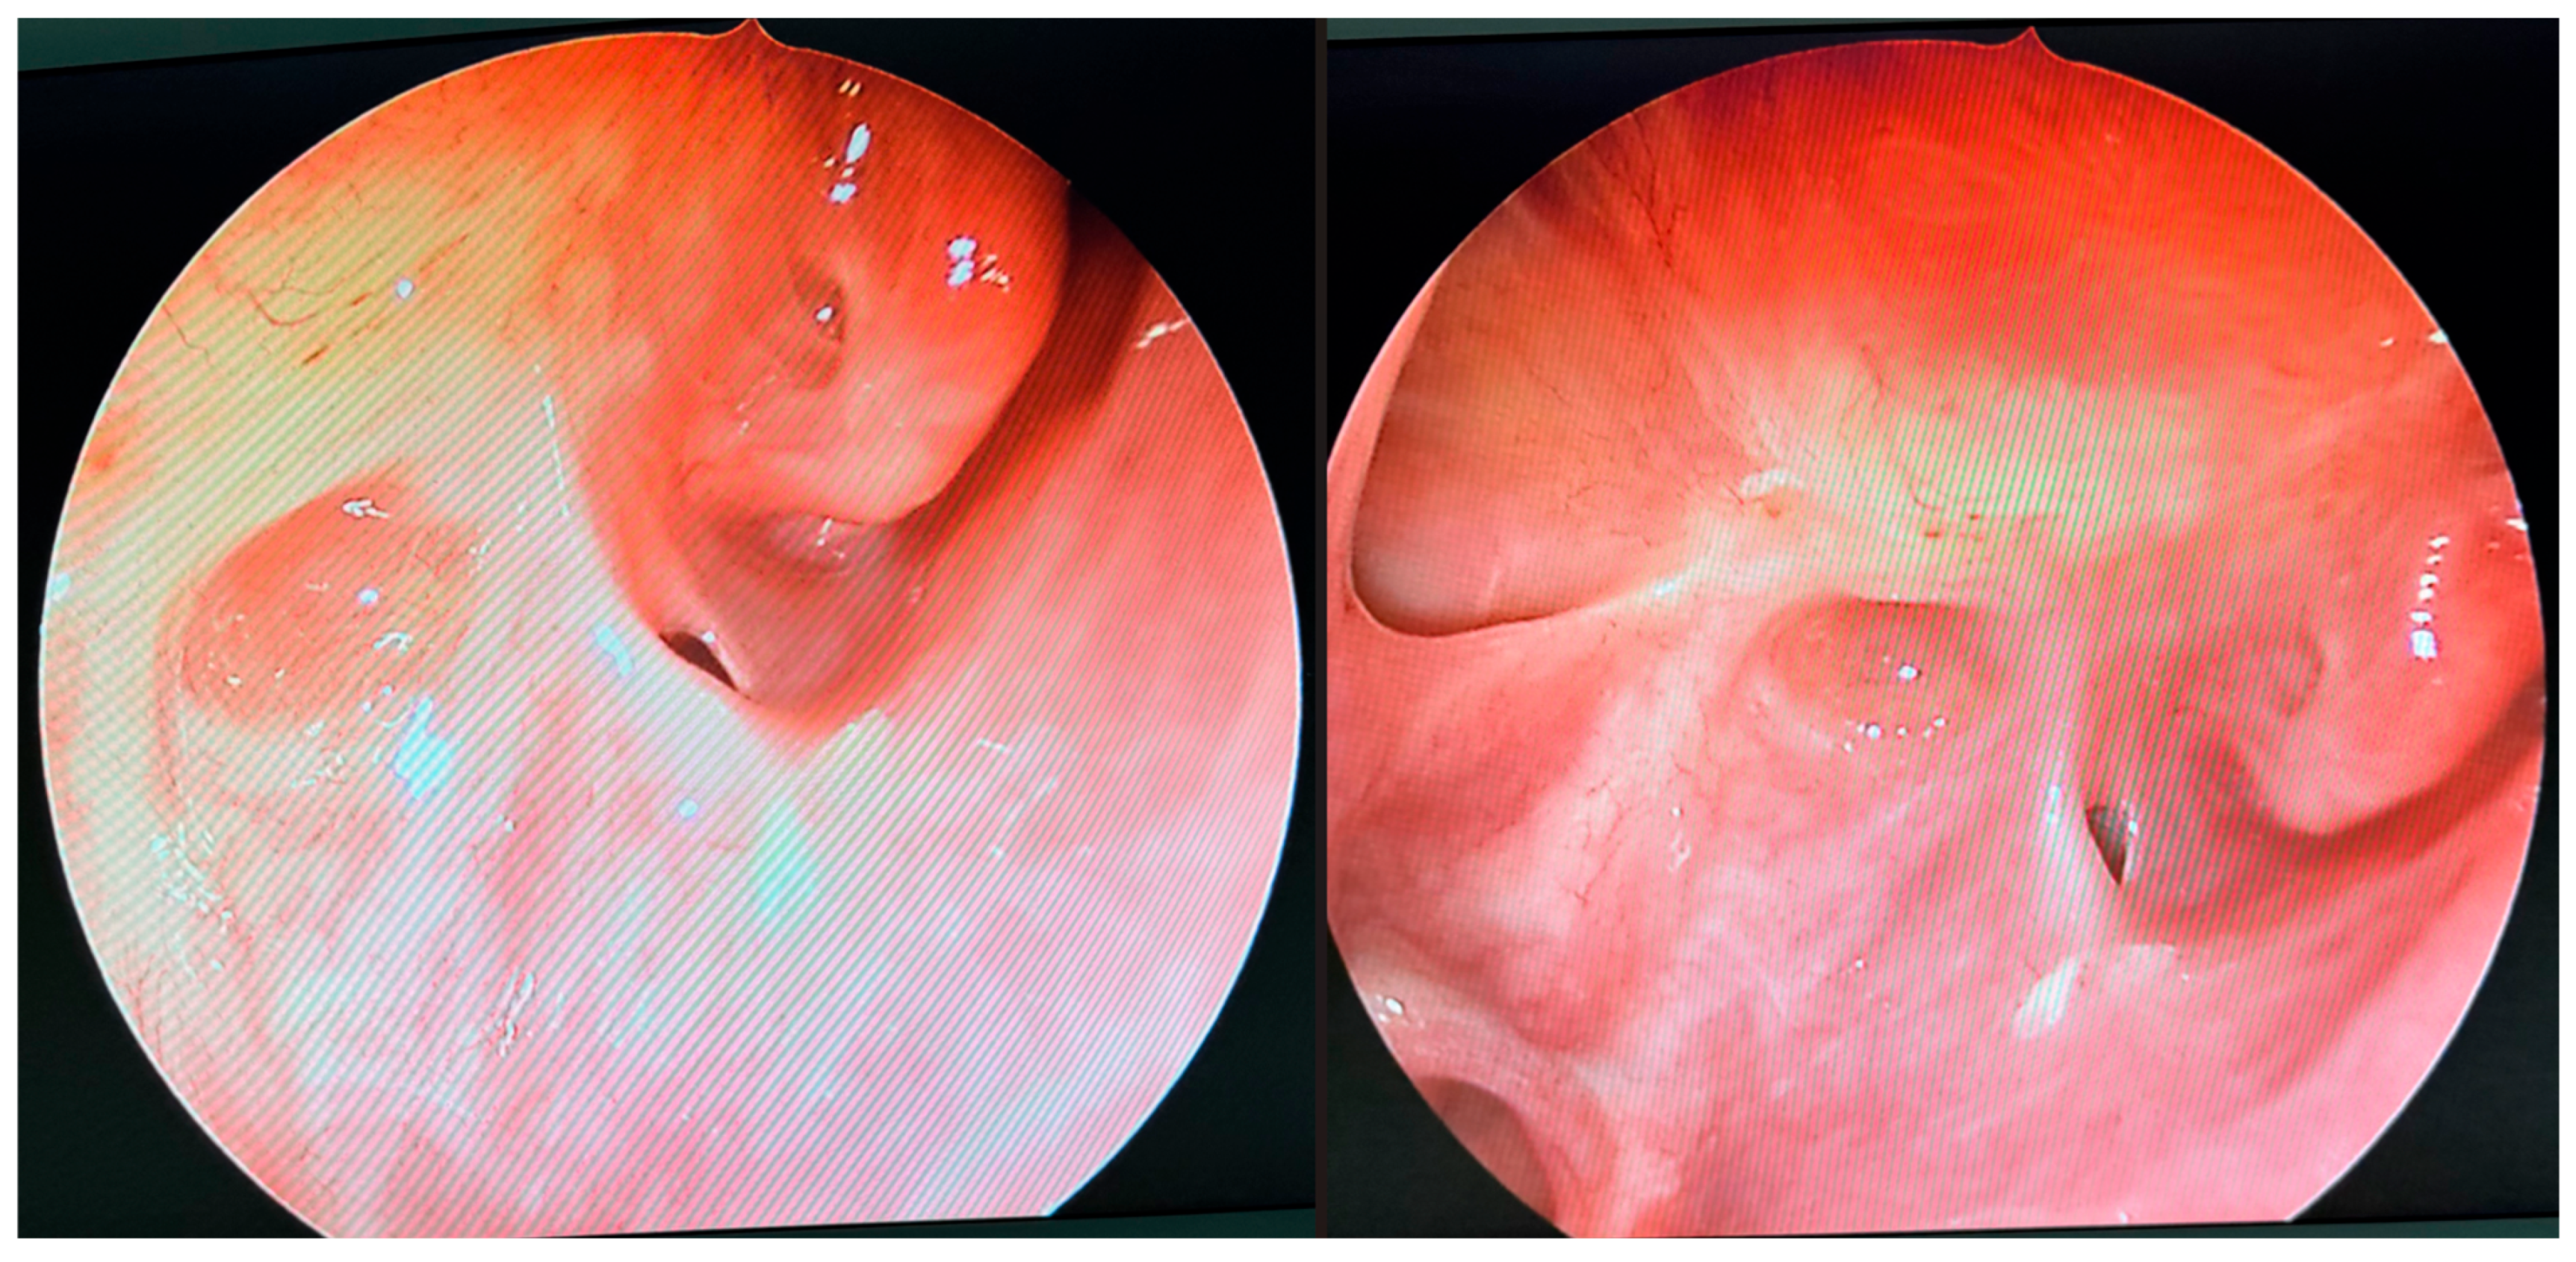

During further inspection, a bony defect of the lamina papyracea was identified in its anterior portion, measuring approximately 4 mm in diameter. The lamina papyracea was resected further, extending posteriorly to the level of the posterior ethmoid cells. A horizontal incision was then made in the orbital periosteum, which allowed for partial herniation of the orbital fat into the ethmoid cavity—facilitating access and drainage. Anterior nasal packing using Merocel was placed to support mucosal healing and maintain patency. Figure 3, Figure 4 and Figure 5 present the intraoperative view.

Figure 3. Endoscopic surgery: intraoperative view showing nasal cavity filled with fungal masses.

Figure 4. Endoscopic surgery: intraoperative view after removal of fungal infiltration to the level of the skull base. Opening of the sphenoidal sinus seen inferiorly (6 o’clock position). The upper-left part of the picture (11 o’clock position) shows the site of orbital periosteum incision with partial herniation of orbital fat into the ethmoid cavity. Two images obtained from the same projection.